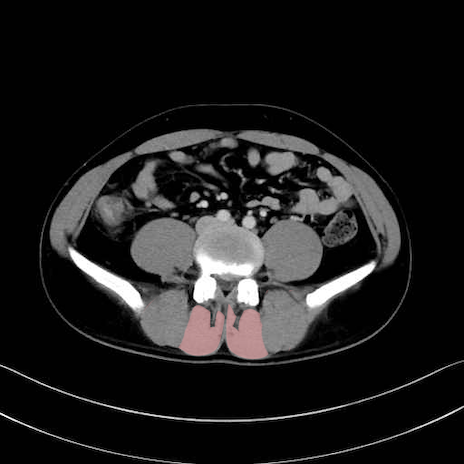

多裂筋 (Multifidus)